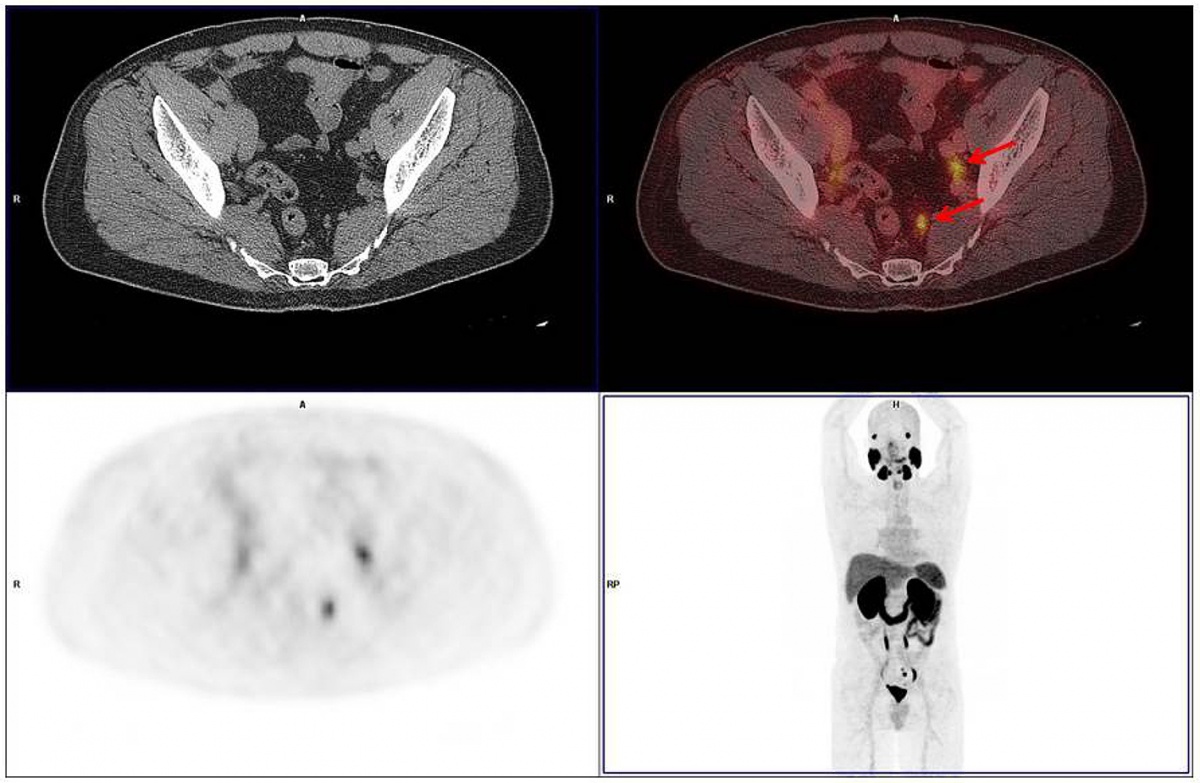

In der Abteilung Nuklearmedizin des BwZKrhs Koblenz wurden seit Juli 2015 insgesamt 193 Untersuchungen mit der PSMA PET/CT durchgeführt. Wir hatten die Gelegenheit in einer ersten Serie von Patienten nach Etablierung der PET/MRT im BwZKrhs Koblenz 34 Patienten, die eine PET/CT erhalten hatten, unmittelbar im Anschluss an diese einer PET/MRT-Untersuchung zuführen zu können (Abbildung 3).

Im dritten Fall wies das PET/MRT vier lymphogene Metastasen auf, während in der PET/CT lediglich zwei Lymphknotenfiliae eindeutig abgrenzbar waren.